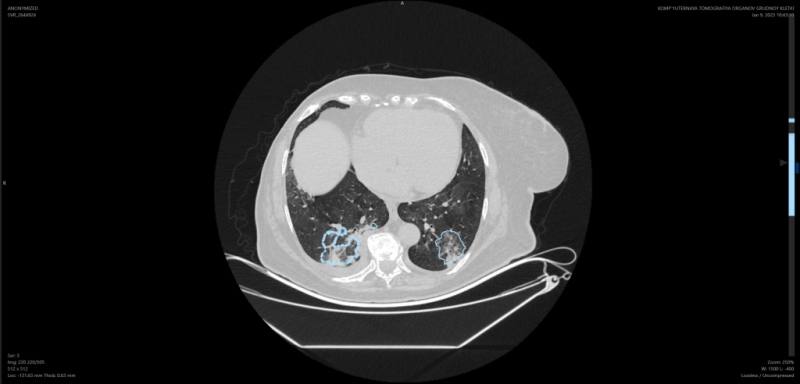

Инновации в сфере медицины развивают и в Калужской области. Компания «Медицинские скрининг системы» стала первой в России разработчиком медицинского искусственного интеллекта, получившим на свои решения регистрационное удостоверение медизделия по наивысшему классу риска. Платформа «Цельс» анализирует цифровые медицинские исследования, подсвечивает признаки патологий – в том числе онкологии на ранних стадиях. На данный момент реализовано четыре направления диагностики: маммография, флюорография, рентгенография ОГК, КТ органов грудной клетки и КТ головного мозга.